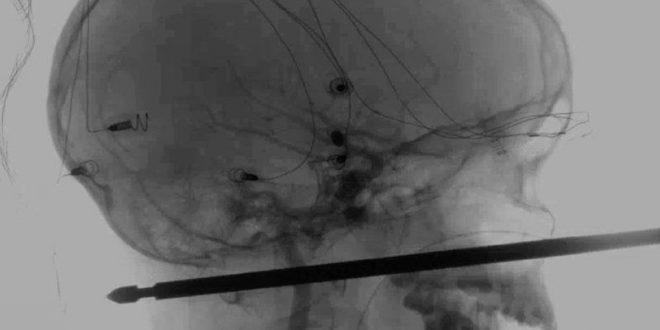

Un niño de 10 años se recupera después de que cayó de un árbol en su casa de Missouri sobre una brocheta de carne. La aguja metálica le entró por la cara y le salió por arriba del cuello,atravesándole la cabeza.

Milagrosamente, hasta allí llegó la mala suerte de Xavier Cunningham. El palillo metálico no pasó por los ojos del menor, la médula espinal ni ningún vaso sanguíneo, reportó el diario The Kansas City Star.

La tragedia de Xavier comenzó el sábado por la tarde cuando unas abejas lo atacaron mientras él estaba en una casita de árbol en su casa de Harrisonville, a unos 56 kilómetros al sur de Kansas City. Cayó al suelo y su madre, Gabrielle Miller, bajó corriendo las escaleras cuando escuchó sus gritos. La brocheta le había atravesado la cabeza y unos 15 centímetros de la estaca le sobresalía por la cara.

No tenía un derrame activo, lo cual dio tiempo para que el hospital reuniera el personal y lo operara el domingo por la mañana. La operación se complicó porque la brocheta no era cilíndrica sino cúbica y tenía que salir muy rectamente para evitar que los bordes le hicieran más daño.